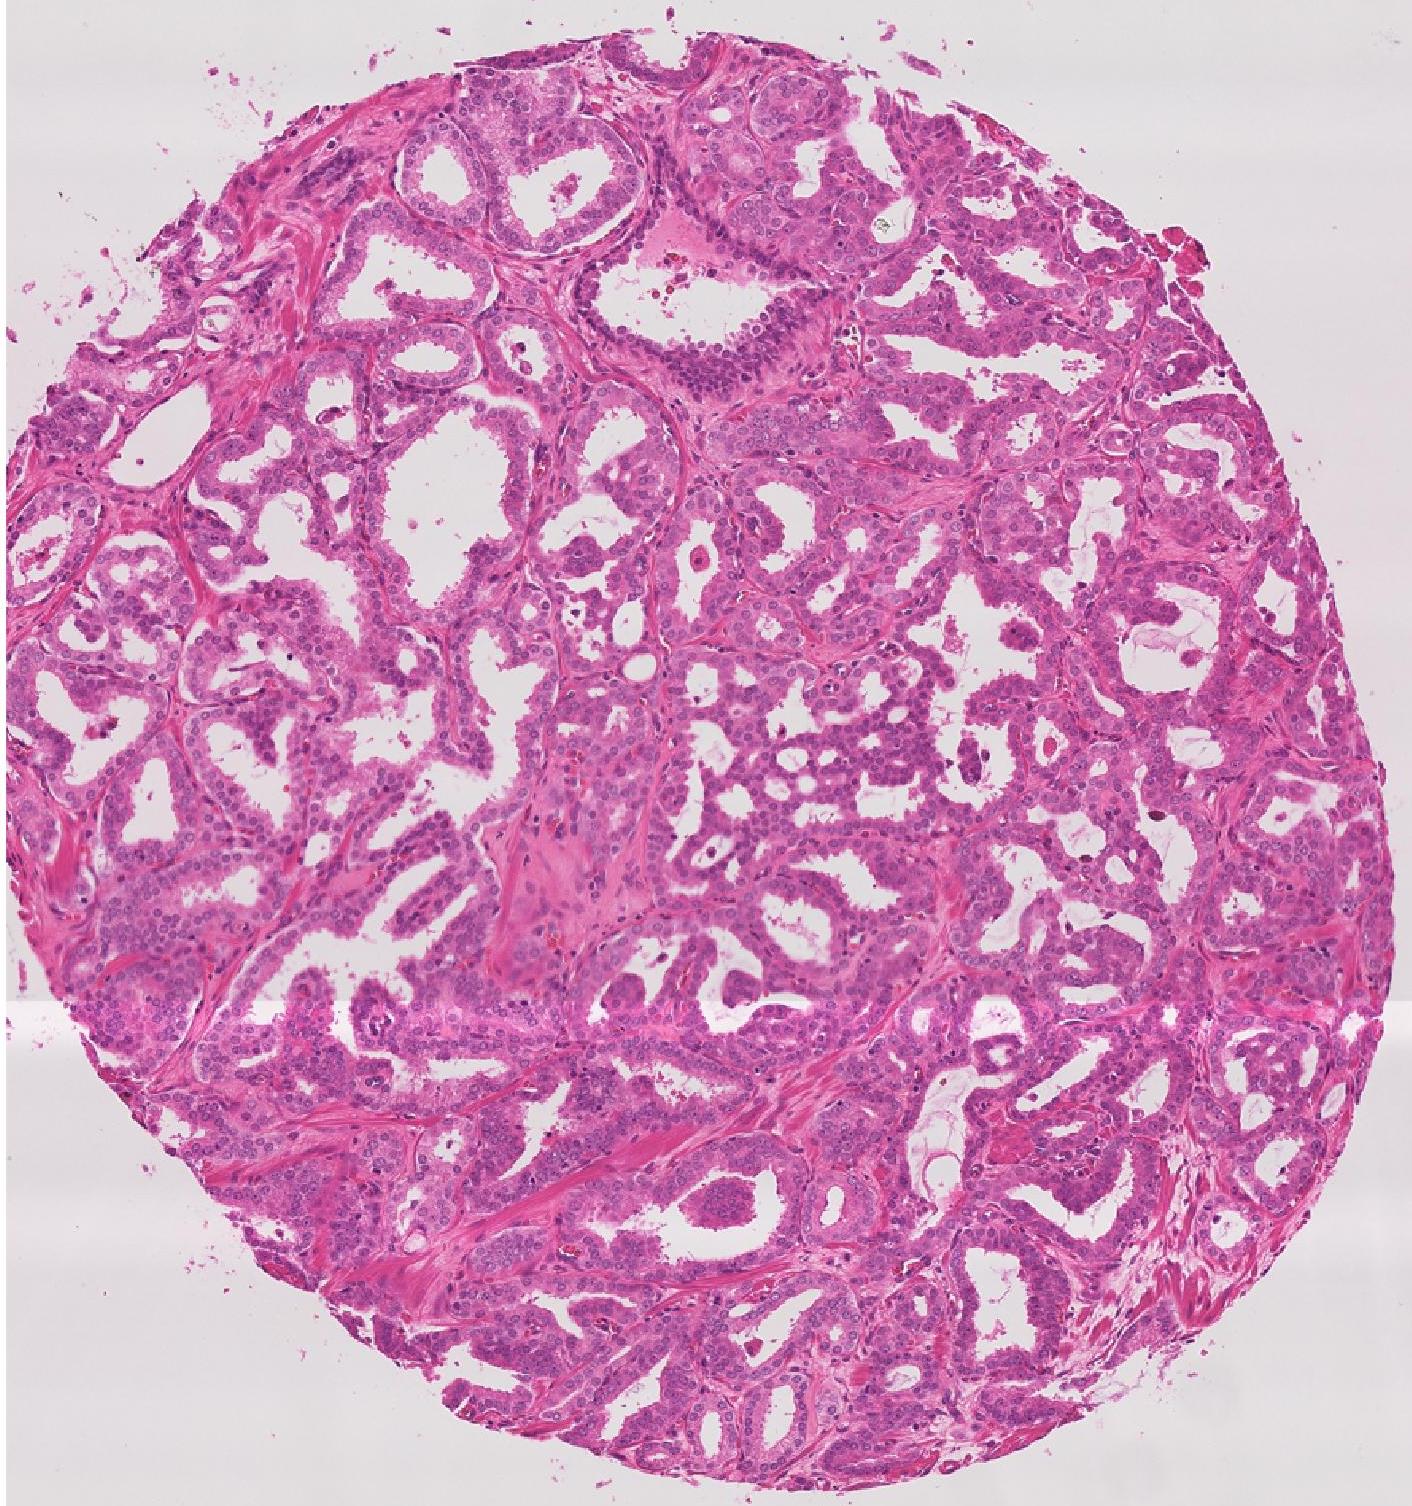

Figure 6 shows the segmentation results using a UNet++ trained on images from different image synthesis methods. Figure 6 (a) shows the test image and Figure 6 (b) shows the manual mask. Figures 6 (c)-(f) show, respectively, the segmentation masks obtained by GeoGANWSS, [38],[39], and . GeoGANWSS’s DM is higher than the DM value of the best performing method. Our results clearly show that modeling geometrical features leads to better performance than state of the art segmentation network architectures.